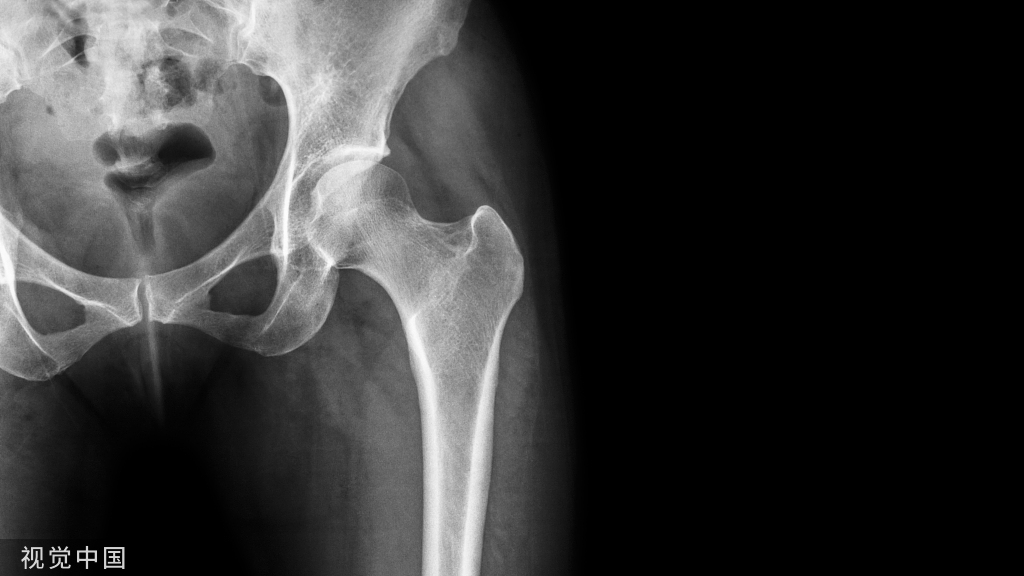

病例特点:男性,32岁,两米高坠落,闭合骨折,分型43A2

治疗:内固定?腓骨固定吗?腓骨先固定吗?下胫腓关节?术后X线片:复位顺序?复位质量?内固定选择?内固定位置?钉数与布局?预后?